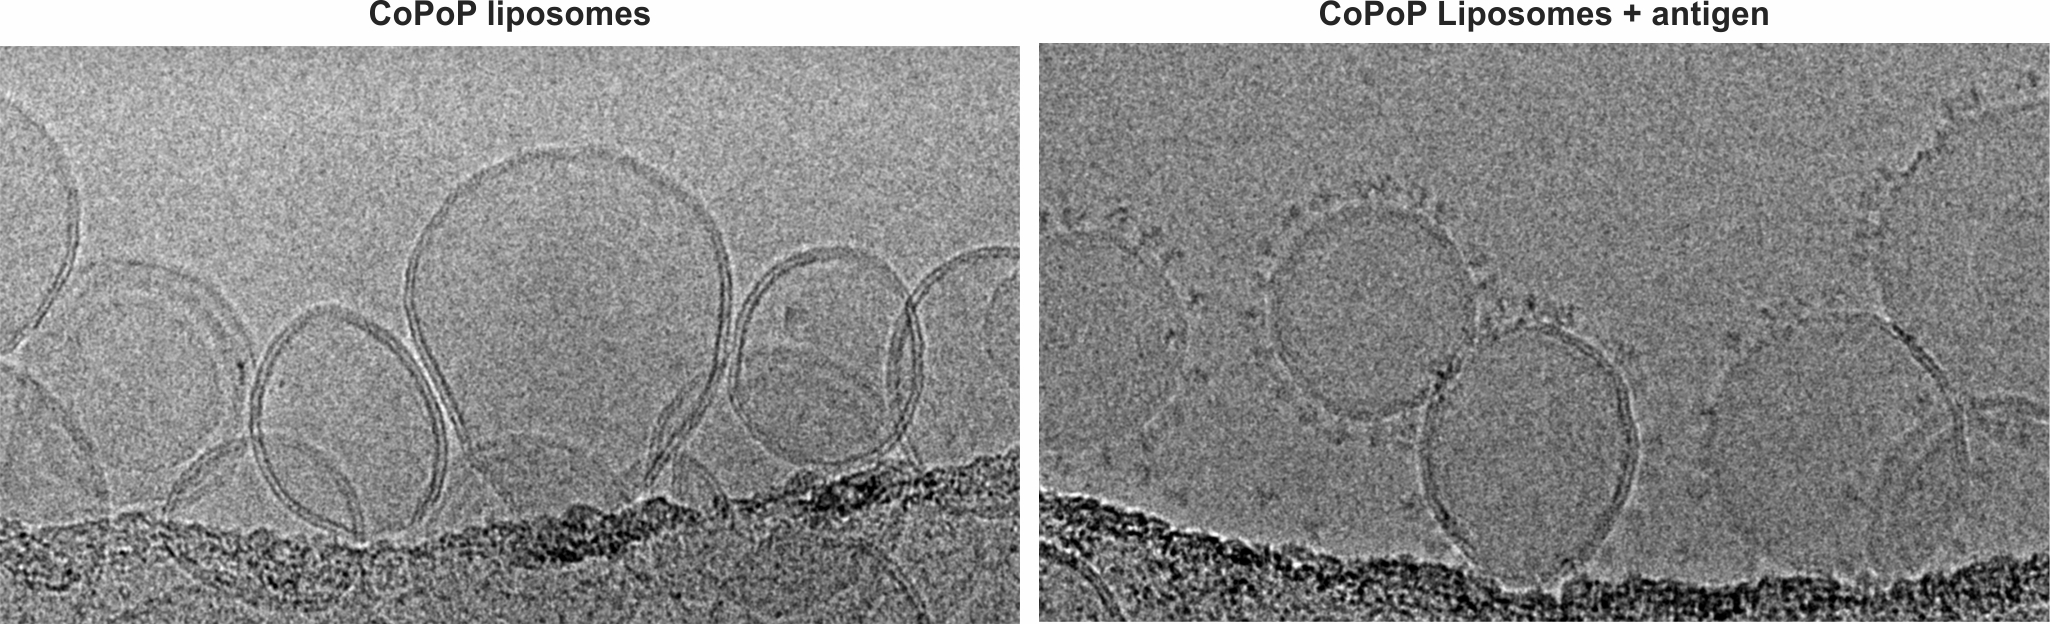

University at Buffalo spinoff POP Biotechnologies’ vaccine delivery platform consists of specialized liposomes that bind to vaccine antigens. Transmission electron microscopy images show some of these liposomes with and without antigens attached. Credit: Jonathan Lovell / University at Buffalo

POP BIO’s vaccine delivery platform is called SNAP (Spontaneous Nanoliposome Antigen Particleization). SNAP consists of specialized liposomes, originally developed in Lovell’s UB lab, that bind to and improve the effectiveness of vaccine antigens — molecules that prompt the body to produce antibodies that neutralize disease.